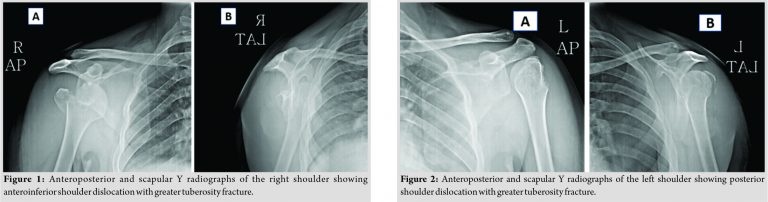

Anteroposterior and scapular Y-view radiographs of the right shoulder (Fig. 1) revealed an anteroinferior dislocation of the shoulder with a displaced fracture of the greater tuberosity and a large Hill–Sachs lesion. Similar views of the left shoulder revealed a light bulb sign (Fig. 2), suggesting posterior dislocation of the shoulder, along with a displaced fracture of the greater tuberosity. Closed reduction of both shoulders was performed with gentle traction under general anesthesia. The greater tuberosities were persistently displaced after the reduction. A lateral transdeltoid approach (deltoid splitting) was used to approach the fracture and transosseous suture fixation of the greater tuberosities with No. 2 Ethibond sutures was done by the technique suggested by Dimakopoulos et al. [3].